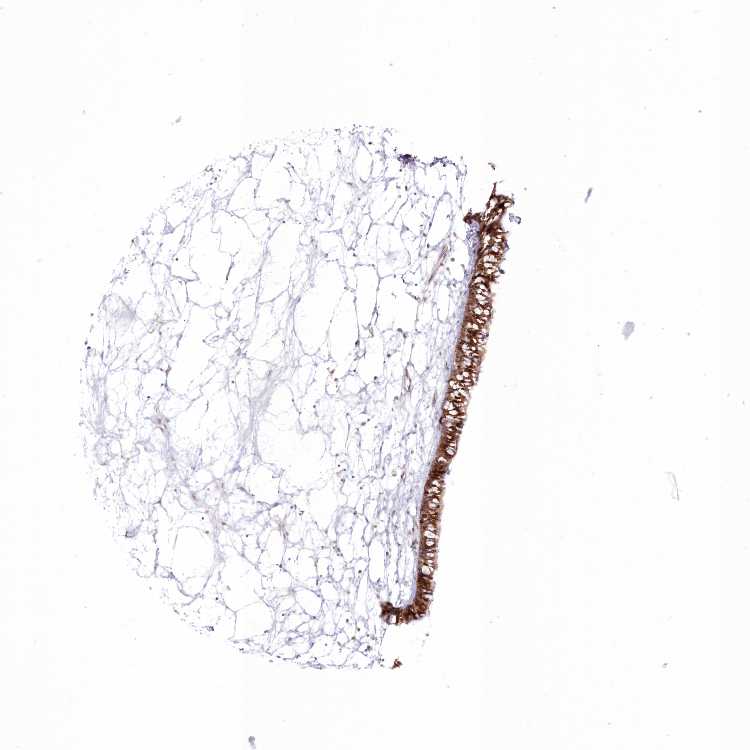

RNPEP